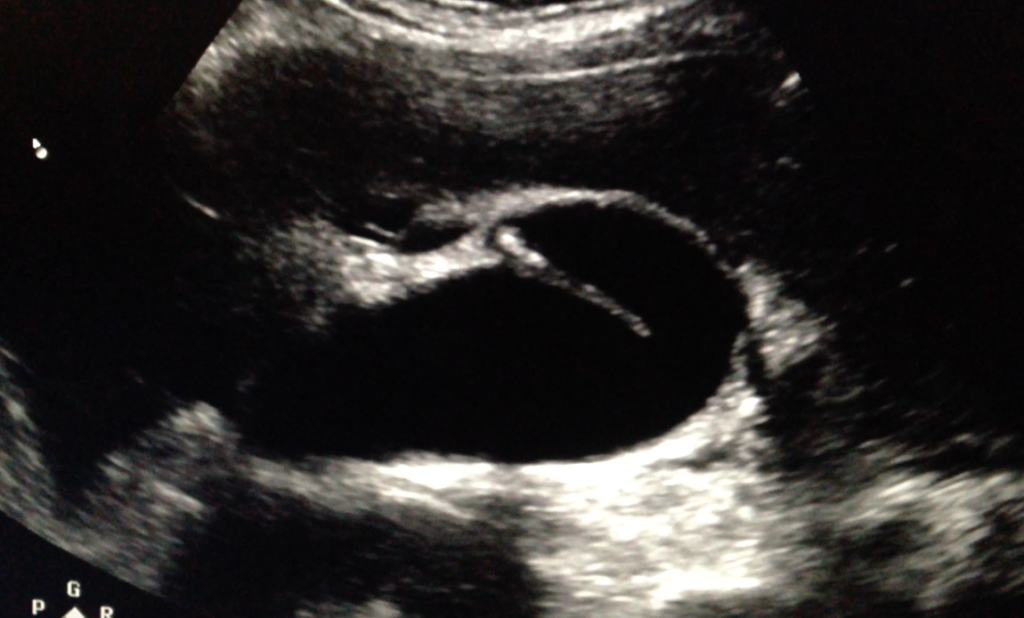

Hartmann's pouch

Hartmann’s pouch

aka infundibulum

outpouching near GB neck

small part of GB that lies near cystic duct where stones may collect